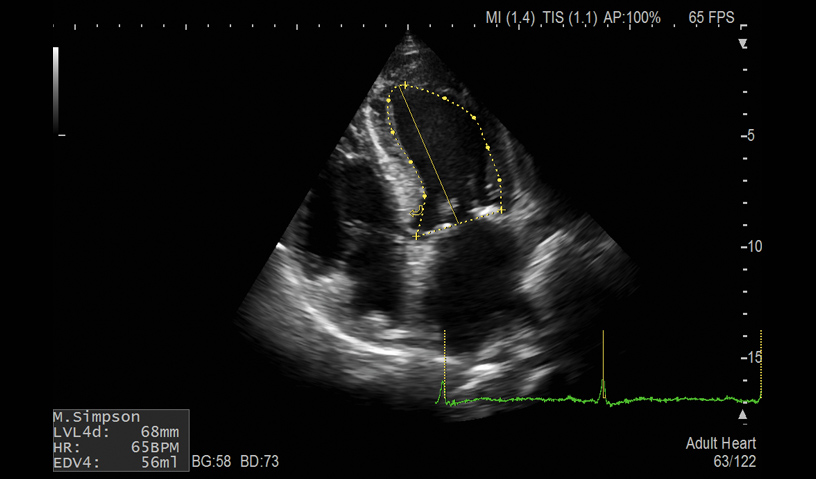

LV Volume (EF)

- Auto LV, LA and RA Volume and FAC